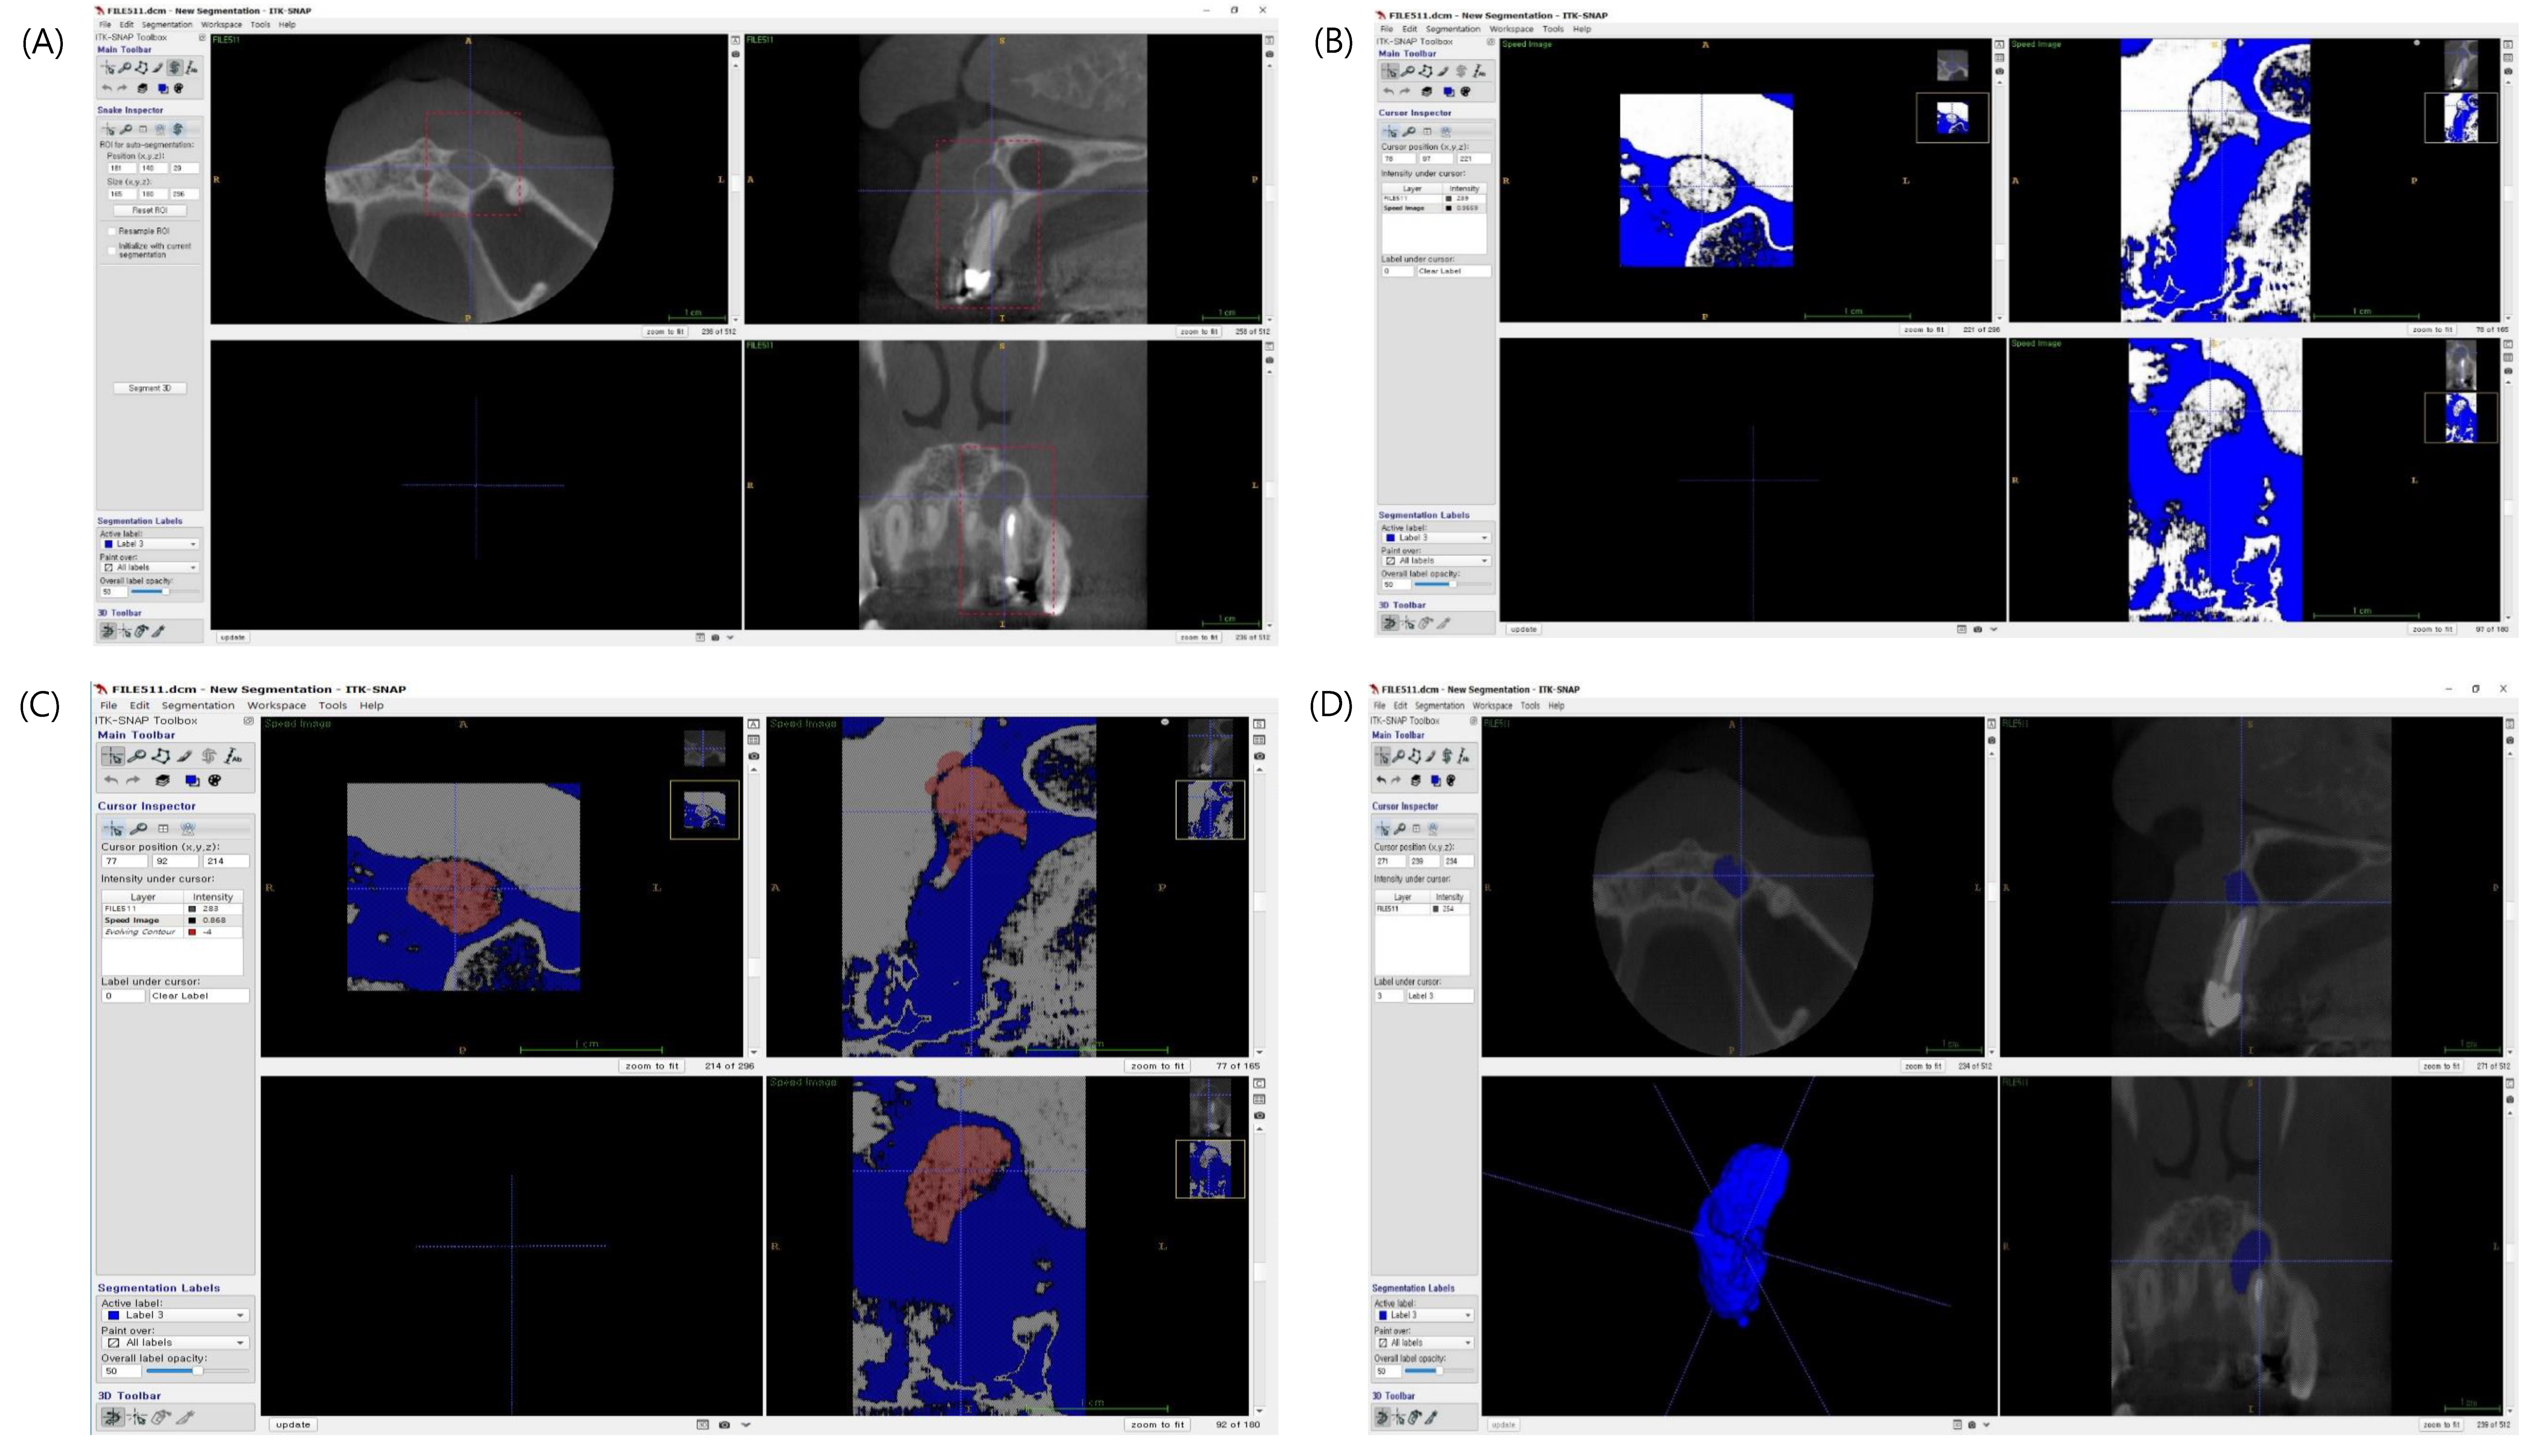

1. Introduction

2.2. Radiography

2.3.2. 3D Radiographic Healing Assessment

2.3.3. Calculation of Lesion Volume in CBCT